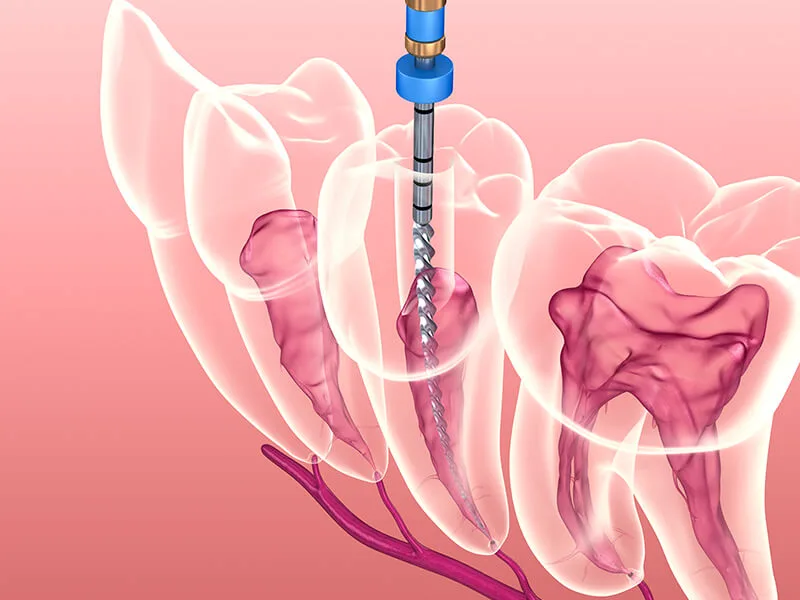

Com o suporte de profissionais qualificados, a endodontia promove um atendimento eficaz e protegido. A especialização dos dentistas nesta área proporciona um conhecimento aprofundado sobre a anatomia das raízes, resultando em intervenções precisas.

Uma unidade focada em endodontia utiliza métodos técnicos que elevam a taxa de sucesso dos procedimentos. O conhecimento específico dos especialistas permite identificar problemas complexos que poderiam passar despercebidos em avaliações básicas:

Realização de tratamentos em canais radiculares com alta precisão anatômica.